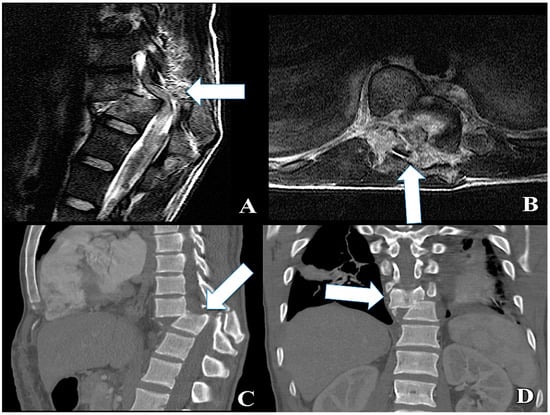

2.1. Traumatic SCI: Clinical Findings